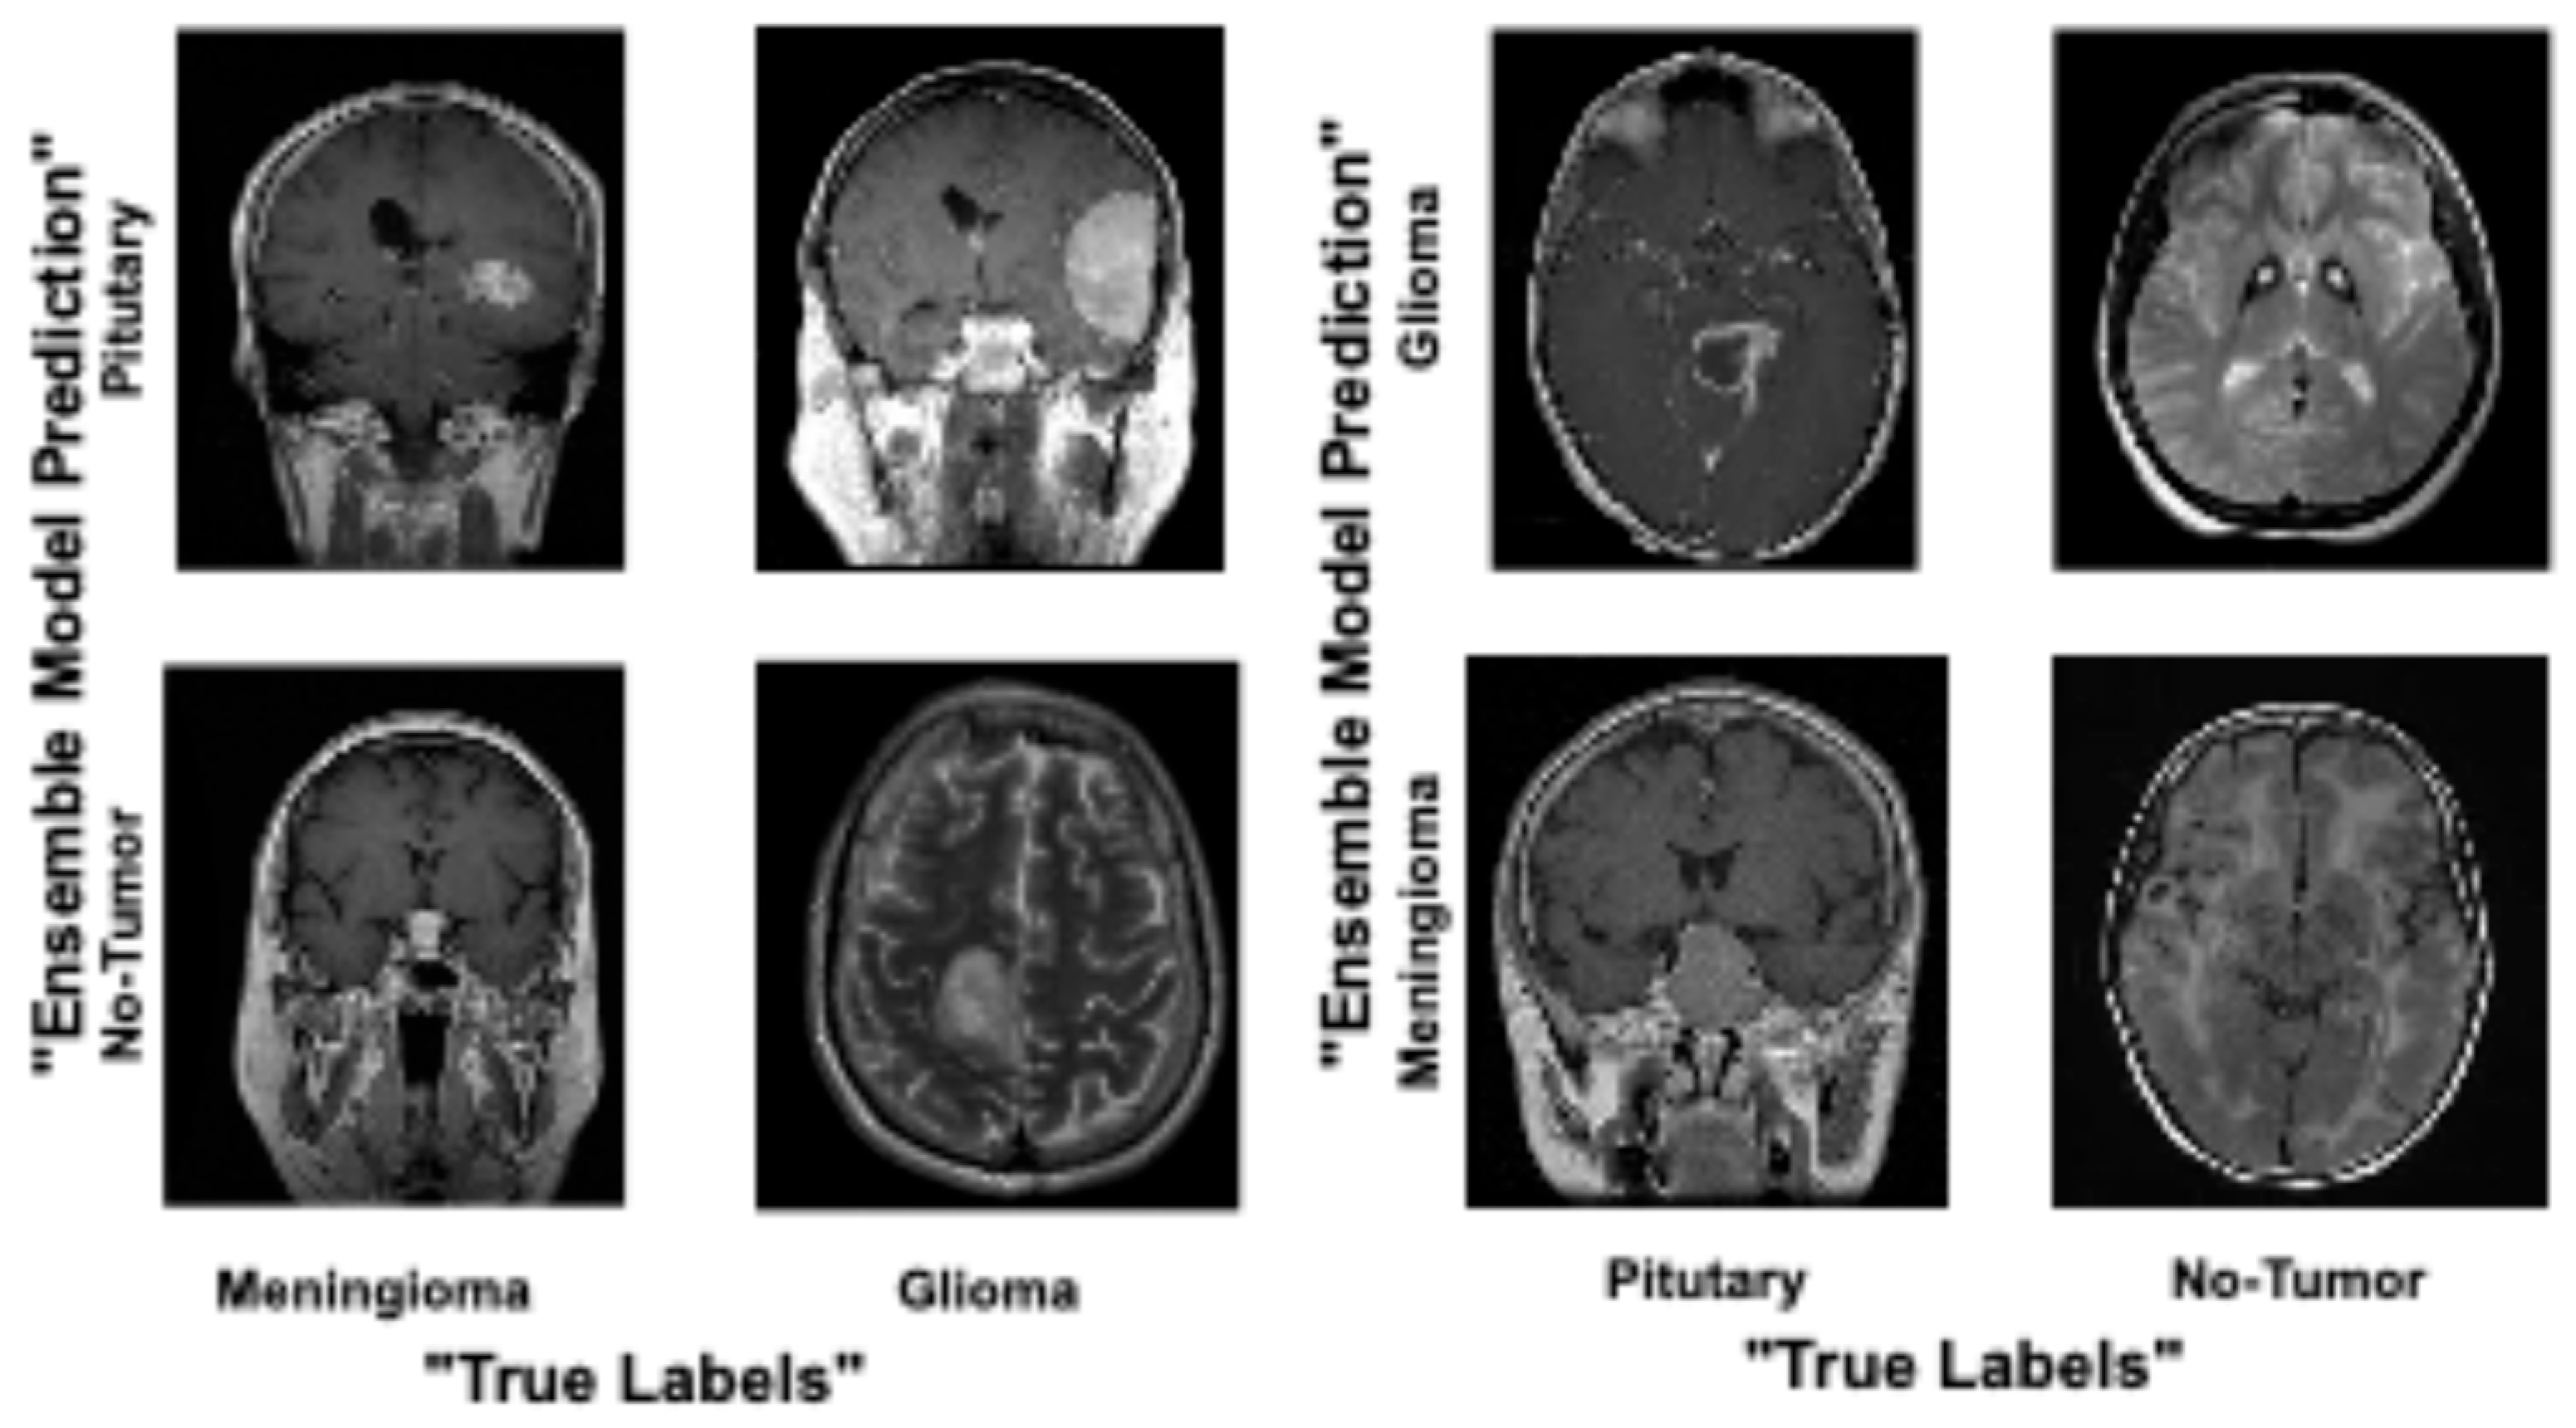

4. Results and Analysis

Comparison of Proposed Ensemble Model vs. Latest Techniques